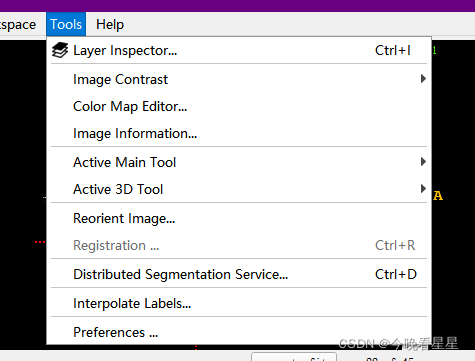

2. Tool 工具的使用

2.1 Lager Inspect 查看图像的信息

- 包括主图信息与标注信息

Contrast可用于调整窗宽窗位,主要是图像的对比度Color Map可用于调节显示的颜色,比如调节为伪彩,便于观察, 但常用的还是灰度图

info与metadata展示图像的基本信息